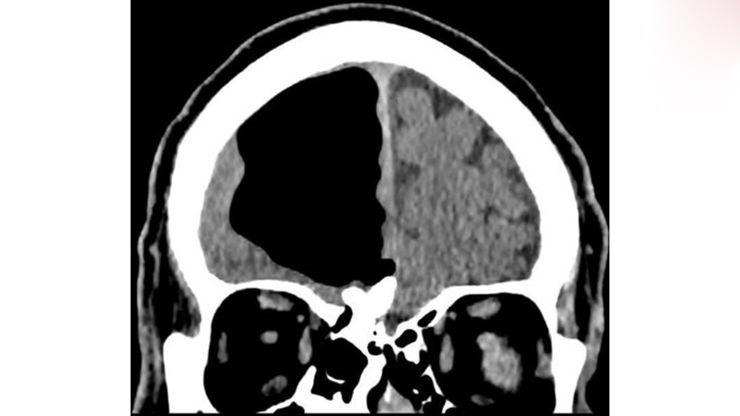

اگر چه نتیجه آزمایش خون این فرد طبیعی بود ولی تصویربرداریها از مغز او وجود یک حفره عجیب ۹ سانتی متری از هوا را در جمجمه نشان میداد.

پس از بررسی تصاویر اسکن مغزی این مرد ایرلندی، پزشکان در مورد علت وجود این حفره تردید داشته و احتمال اختلالات مادرزادی یا عملهای جراحی پیشین این فرد را مطرح کردند که خود این فرد انجام هر گونه عمل جراحی یا وجود اختلالات مادرزادی را تکذیب کرد.

این حفره به عنوان یک پنوماتوسل، حفرهای پرفشار از هوا، در سمت راست لوب پیشانی این فرد قرار گرفته است.این دسته از حفرهها معمولا در بیمارانی که سابقه جراحی مغز یا ابتلا به انواع مختلف عفونت را داشتهاند معمول است ولی اندازه آنها بسیار کوچکتر است.

اسکن مغزی همچنین یک تومور خوش خیم استخوانی و یک سکته ناقص در مغز او را نشان داد. به منظور درمان این حفره، پزشکان پیشنهاد جراحی به او را دادند که با توجه به خطرات ناشی از جراحی، این مرد ایرلندی پیشنهاد را نپذیرفت ولی در عوض قرار شد انواع مختلفی از داروها را برای کمک به پیشگیری از سکتههای آینده دریافت کند.